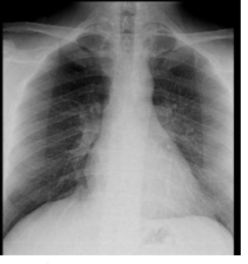

What is this and what type of scan

PA CXR

Label this CXR (10 things)

1) trachea 2) hilum- should have R and L 3) lungs 4) diaphragm 5) heart 6) aortic knuckle 7) ribs 8) scapulae 9) breasts 10) bowel gas